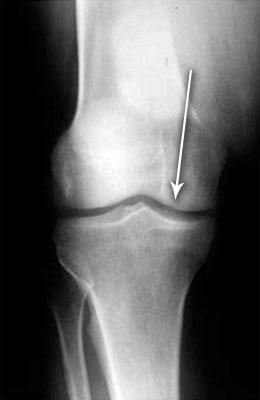

Uitați-vă la aceste imagini, puteți vedea că în imaginea din dreapta nu există spațiu articular, oasele se freacă unele de altele, provocând dureri puternice. Iar acest proces este foarte greu de oprit! În câțiva ani, persoana va deveni invalidă și nu va mai fi capabilă să aibă grijă de sine.